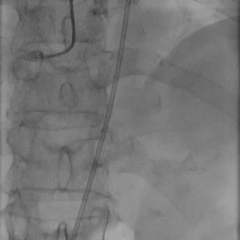

术中影像

左冠造影

左冠狭窄处行PCI处理

PCI后左冠造影,血流通畅

右冠造影

右冠狭窄处行PCI处理

PCI后右冠造影,血流通畅

根部造影,瓣叶活动差

20mm球囊预扩,微腰微漏

输送器过弓

snare辅助下跨瓣